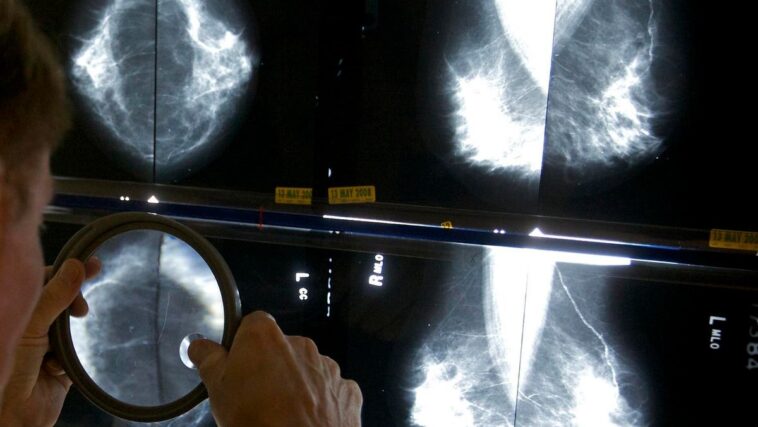

A radiologist uses a magnifying glass to check mammograms for breast cancer

The study enrolled over 80,000 women in a clinical trial to ask this question. All 80,033 underwent mammography. Half of those mammograms were interpreted the standard way in Sweden, which is by two physicians. The other half had their mammograms read by a physician (or two physicians) who had an AI-supported analysis.

What’s an “AI-supported analysis?” That’s when the AI system reviewed the images of the mammogram first, then gave the images a score from 0-10. The image and the score then was reviewed by a radiologist (or two radiologists if the score was 10, the highest risk score).